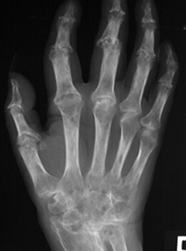

Fig 21. Artropatía reumática.

A: Rx AP de mano. Hallazgo precoz de la enfermedad, con erosión marginal.

B: Estado mas avanzado con varias erosiones en los metacarpianos y las falanges.